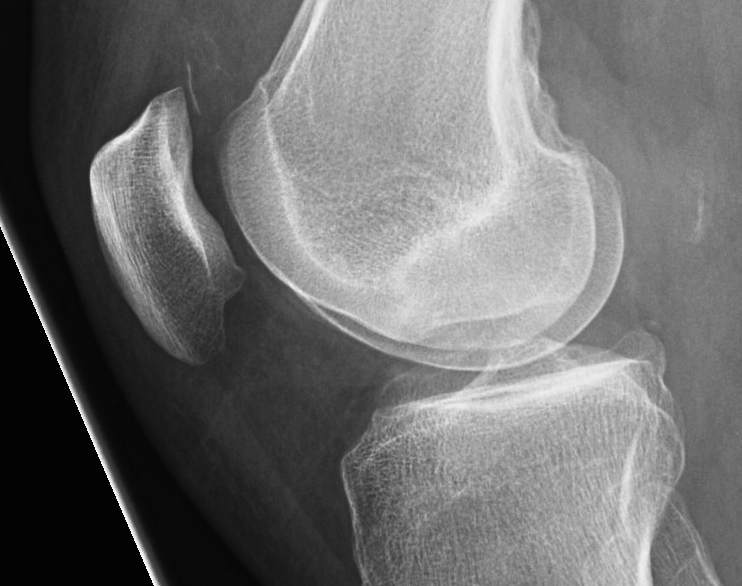

Xray

AP / Lateral / Skyline

- examine carefully for loose body